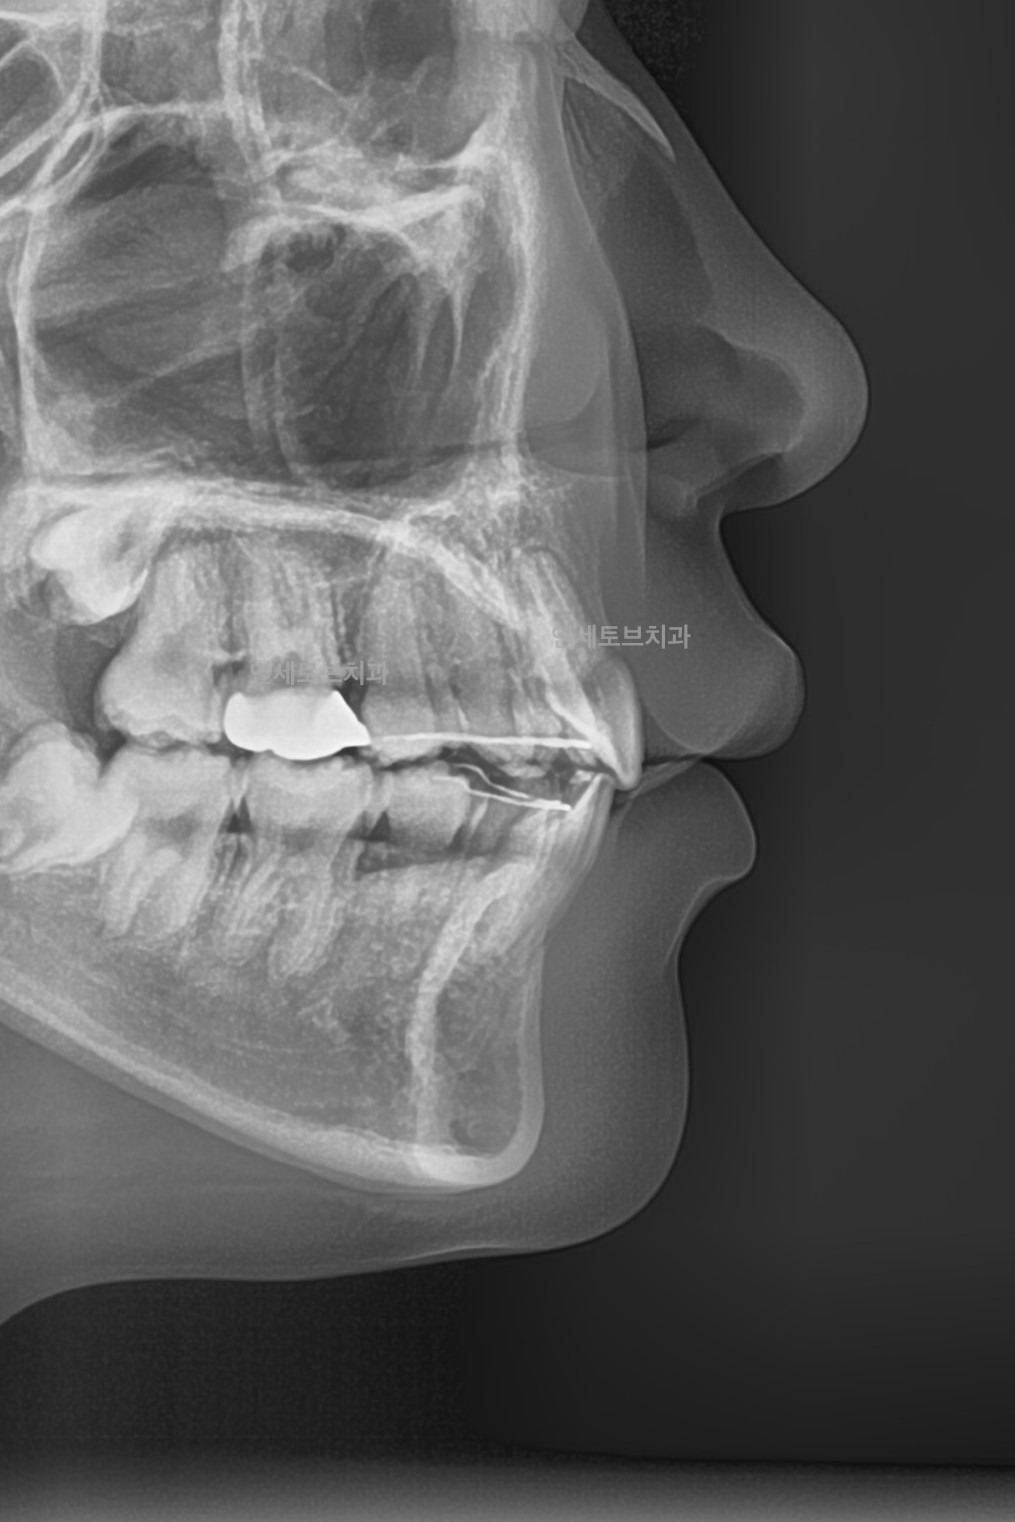

돌출입은 윗니나 아랫니(또는 둘 다)가 정상적인 위치보다 앞으로 튀어나온 상태를 말합니다.

이로 인해 입술이 앞으로 돌출되어 보이고, 측면 얼굴 프로필에서 특히 두드러지게 나타납니다.

After